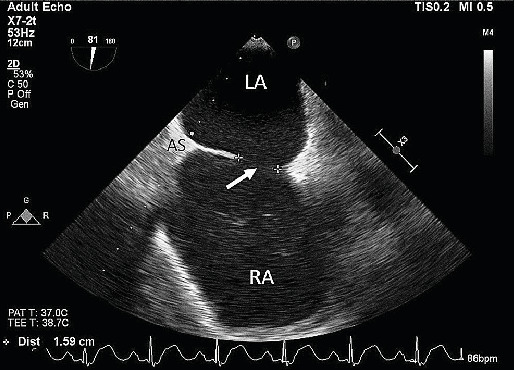

Abstract Image